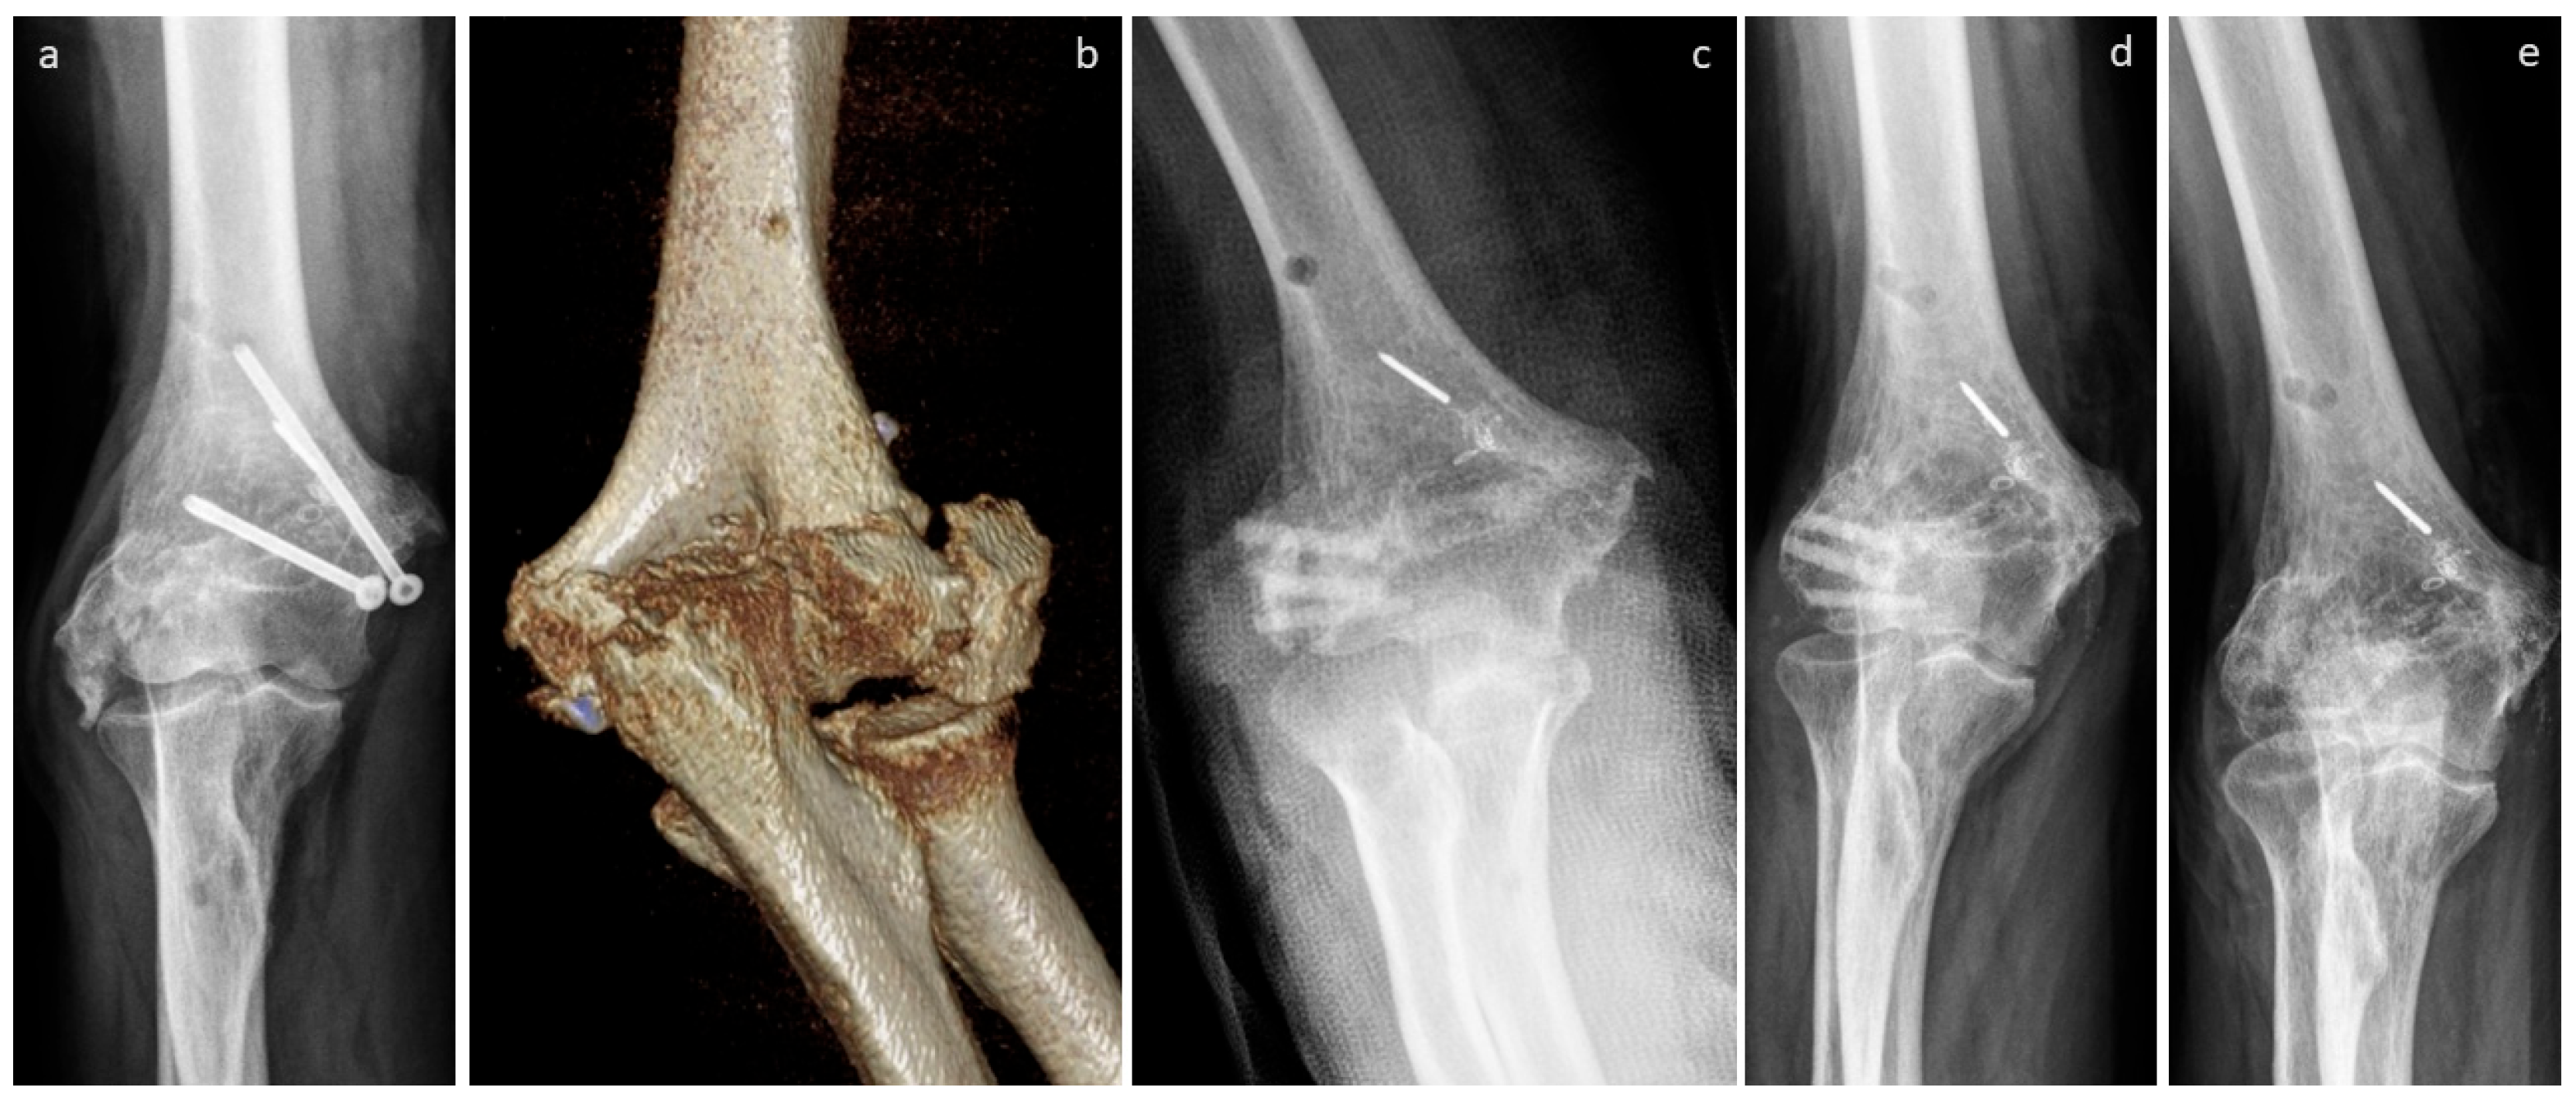

3.4. Selected Case Descriptions